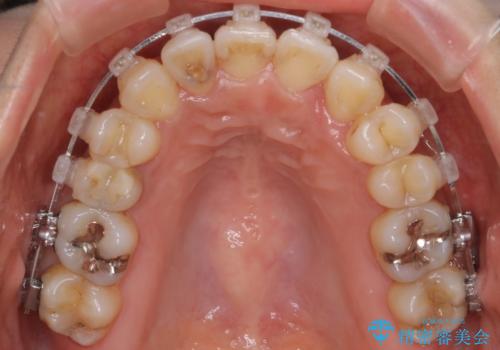

【審美装置】抜歯の本数最小限で行った矯正治療

- 審美装置

- 全体のがたつきを主訴に来院されました。4番目の歯を4本抜歯も検討しましたが、口元が下がりすぎてしまうリスクと2番目の転位うが著しく並べるのにかかる期間を考慮し、変則的な抜歯をし、並べる計画を立てました。

抜歯矯正のため2年はかかってしまいましたが、きれいに並び患者様にも満足頂きました。